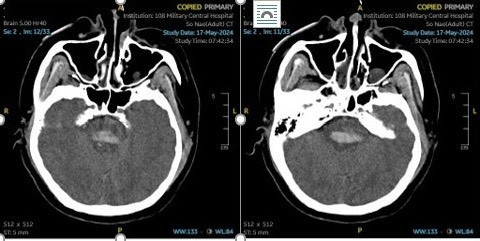

Tổn thương thân não trên phim chụp - Ảnh BVCC

Do đang công tác tại Việt Nam, anh được các đồng nghiệp nhanh chóng đưa bệnh nhân vào bệnh viện tỉnh Bắc Ninh, chụp CT sọ não được chẩn đoán chảy máu não vùng thân não do tăng huyết áp không kiểm soát. Sau đó anh được chuyển lên Bệnh viện Trung ương Quân đội 108. Khi nhập viện, bệnh nhân trong tình trạng hôn mê, liệt tứ chi, bí tiểu, thở tụt lưỡi...

Tại bệnh viện, các bác sĩ chẩn đoán bệnh nhân xuất huyết thân não do tăng huyết áp. Tổn thương ở thân não đã gây ra các triệu chứng nghiêm trọng như hôn mê, liệt vận động và rối loạn chức năng thần kinh. Ngay lập tức, các bác sĩ tại Khoa Đột quỵ não đã áp dụng các phương pháp chẩn đoán và điều trị đa mô thức, hồi sức thần kinh tích cực.

Bệnh nhân này chảy máu đúng vùng thân não, kích thước khá lớn, thể trạng béo phì, nặng trên 80 kg, huyết áp cao khó kiểm soát, việc điều trị để cứu được tính mạng bệnh nhân thì có thể nhưng khó khăn nhất là phải cứu được tối đa các chức năng thần kinh như ý thức, hô hấp, ngôn ngữ và vận động tử chi, nuốt...